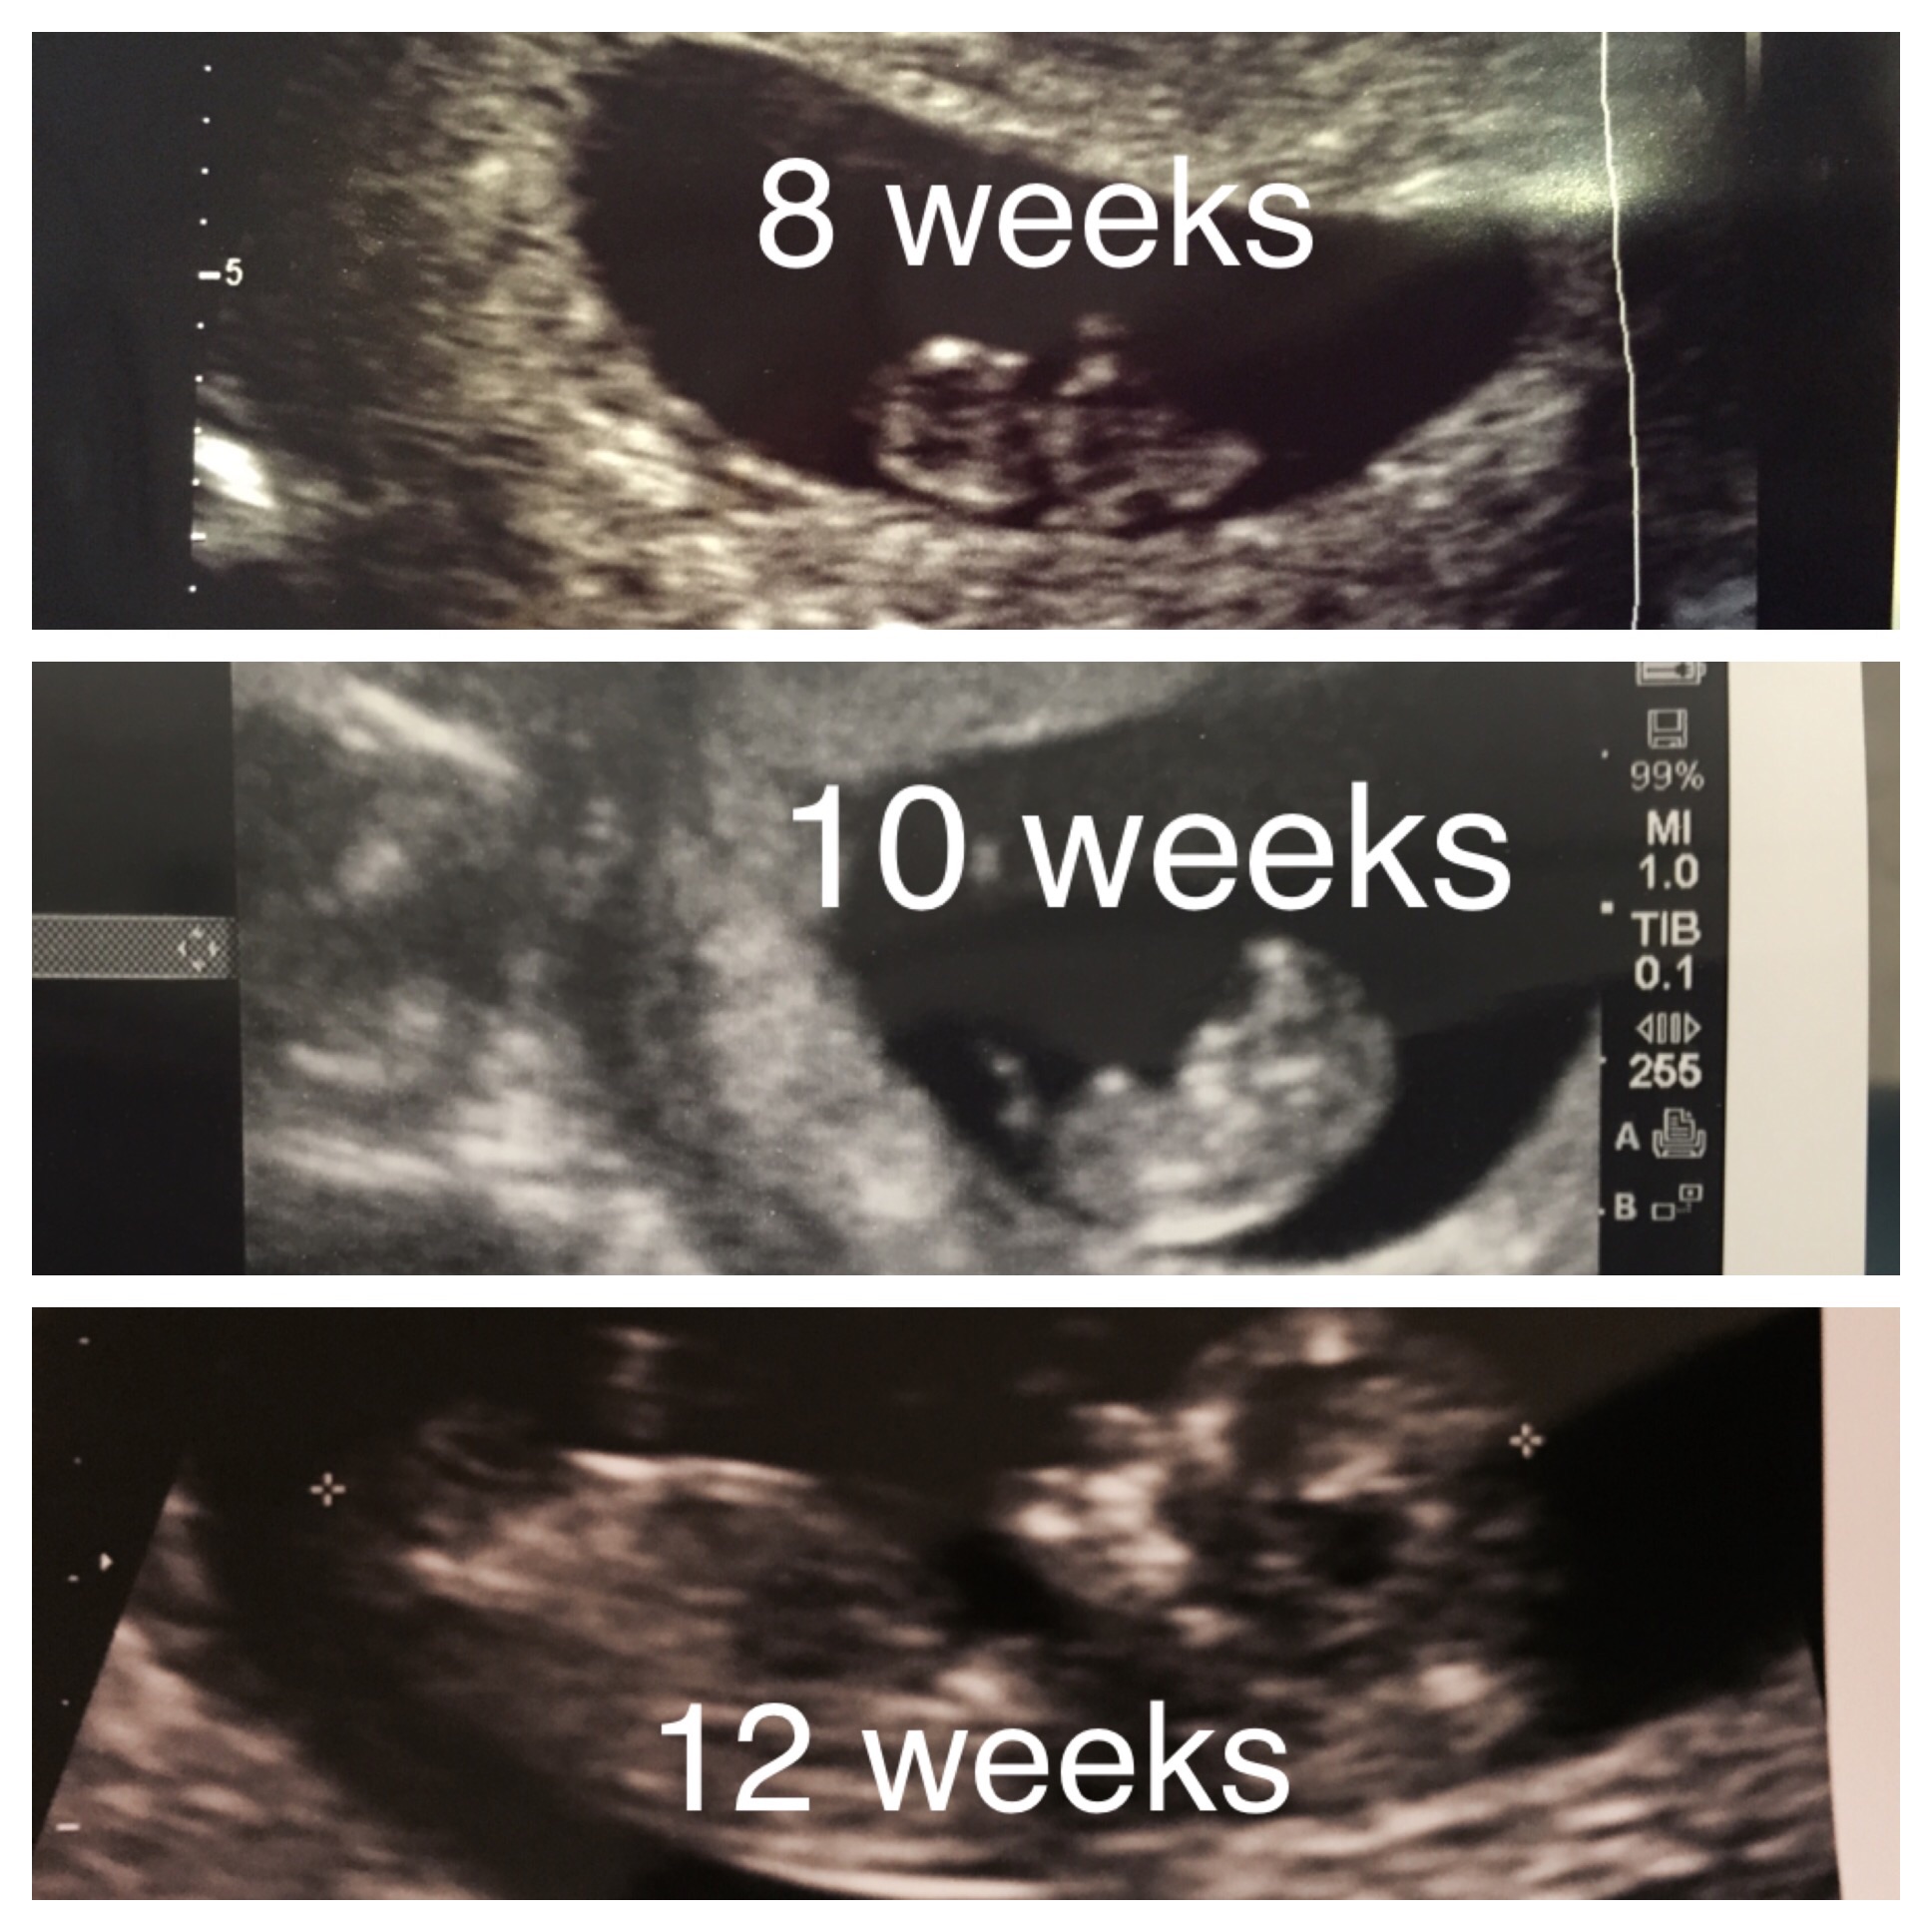

Appointment went well today! Baby continues to grow and has a strong heartbeat. My ob was great too- said that I can come in every 2 weeks instead of every 4 weeks (at least for the next few appointments) so that I don't get so nervous between appointments. I included a picture of our little one- a little blurry, but a baby!! Crazy how small it is!!

My next appt is Oct 7th, I will be 12w4d. I am really excited to see my little one and even though this will be my 3rd u/s I am still very nervous. I passed a milestone with each u/s so far and pray it continues!

Yaayyy! Congratulations to all of you! Loved seeing your nuggets and reading good news, prepped me positively for my appointment today. And boy am I thrilled! Baby measured right on target - in fact two days ahead, but we are sticking to same EDD so 10w4d it is! Heart rate of 165 and peanut was moving about so cutely and waving